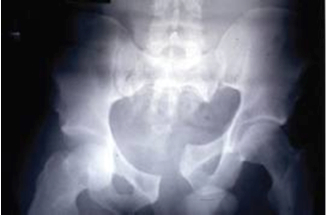

The final group that we have not yet considered in the Young and Burgess classification is the vertical shear group. These patients are complex because the injuries are both horizontally and vertically unstable. You will see what I mean if you have a look at this Xray:

Is putting a binder around the greater trochanters and pulling going to help? Will it produce anatomical realignment? I think you will agree that it is hard to know. In this case it might rotate the left hemipelvis inward and create even more distortion. You might also guess that some traction on the left leg before you apply the binder might get a better result too. More on this later.